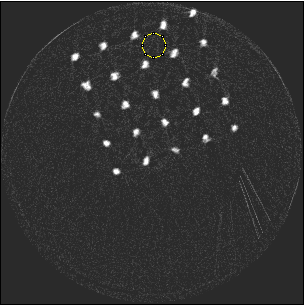

Photon-counting detectors have been successfully employed in preclinical applications. Using spectral imaging, a novel approach towards minimising beam hardening effects is proposed. To the best of our knowledge, beam hardening and metal artefact reduction using spectral imaging has not been reported. Unlike numerical techniques, the work described in this paper aims at minimising metal artefacts in the acquisition stage, by capturing high energy quanta that exhibit less beam hardening effects. The Medipix ASIC allows simultaneous data acquisition from discrete user-defined energy ranges. The ASIC was designed to count photon events and categorise them based on energy thresholds determined by the user. This feature enables the capture of spectral signatures for multiple materials which can be used for material discrimination. The number of counts for discrete energy bands can be obtained by subtracting data from two counters. This is essentially done as a pre-processing step prior to flat-field normalization and reconstruction. The raw data from a counter has an energy range between [TCsubscript𝑇𝐶T_{C}, kVp], where TCsubscript𝑇𝐶T_{C} is the corresponding user-defined threshold and kVp is the x-ray tube potential used. Since the count information is acquired simultaneously in a single exposure, the noise in a particular energy range is local Poisson noise due to quantum fluctuations. Reduction in streak artefacts using spectral imaging of a scaffold sample is shown in figure 1. Wide energy acquisition shows severe streaks while narrow high energy range exhibits reduced artefacts. Also, spatial improvements corresponding to the metal region can be noticed in the narrow energy band while the wide energy reconstruction shows a blooming effect.

Refer to caption

(a) 15 to 80 keV

(b) 55 to 80 keV

Figure 1: Metal scaffold sample imaged using Medipix3RX. High energy range shows reduced artefacts compared to wide energy acquisition.